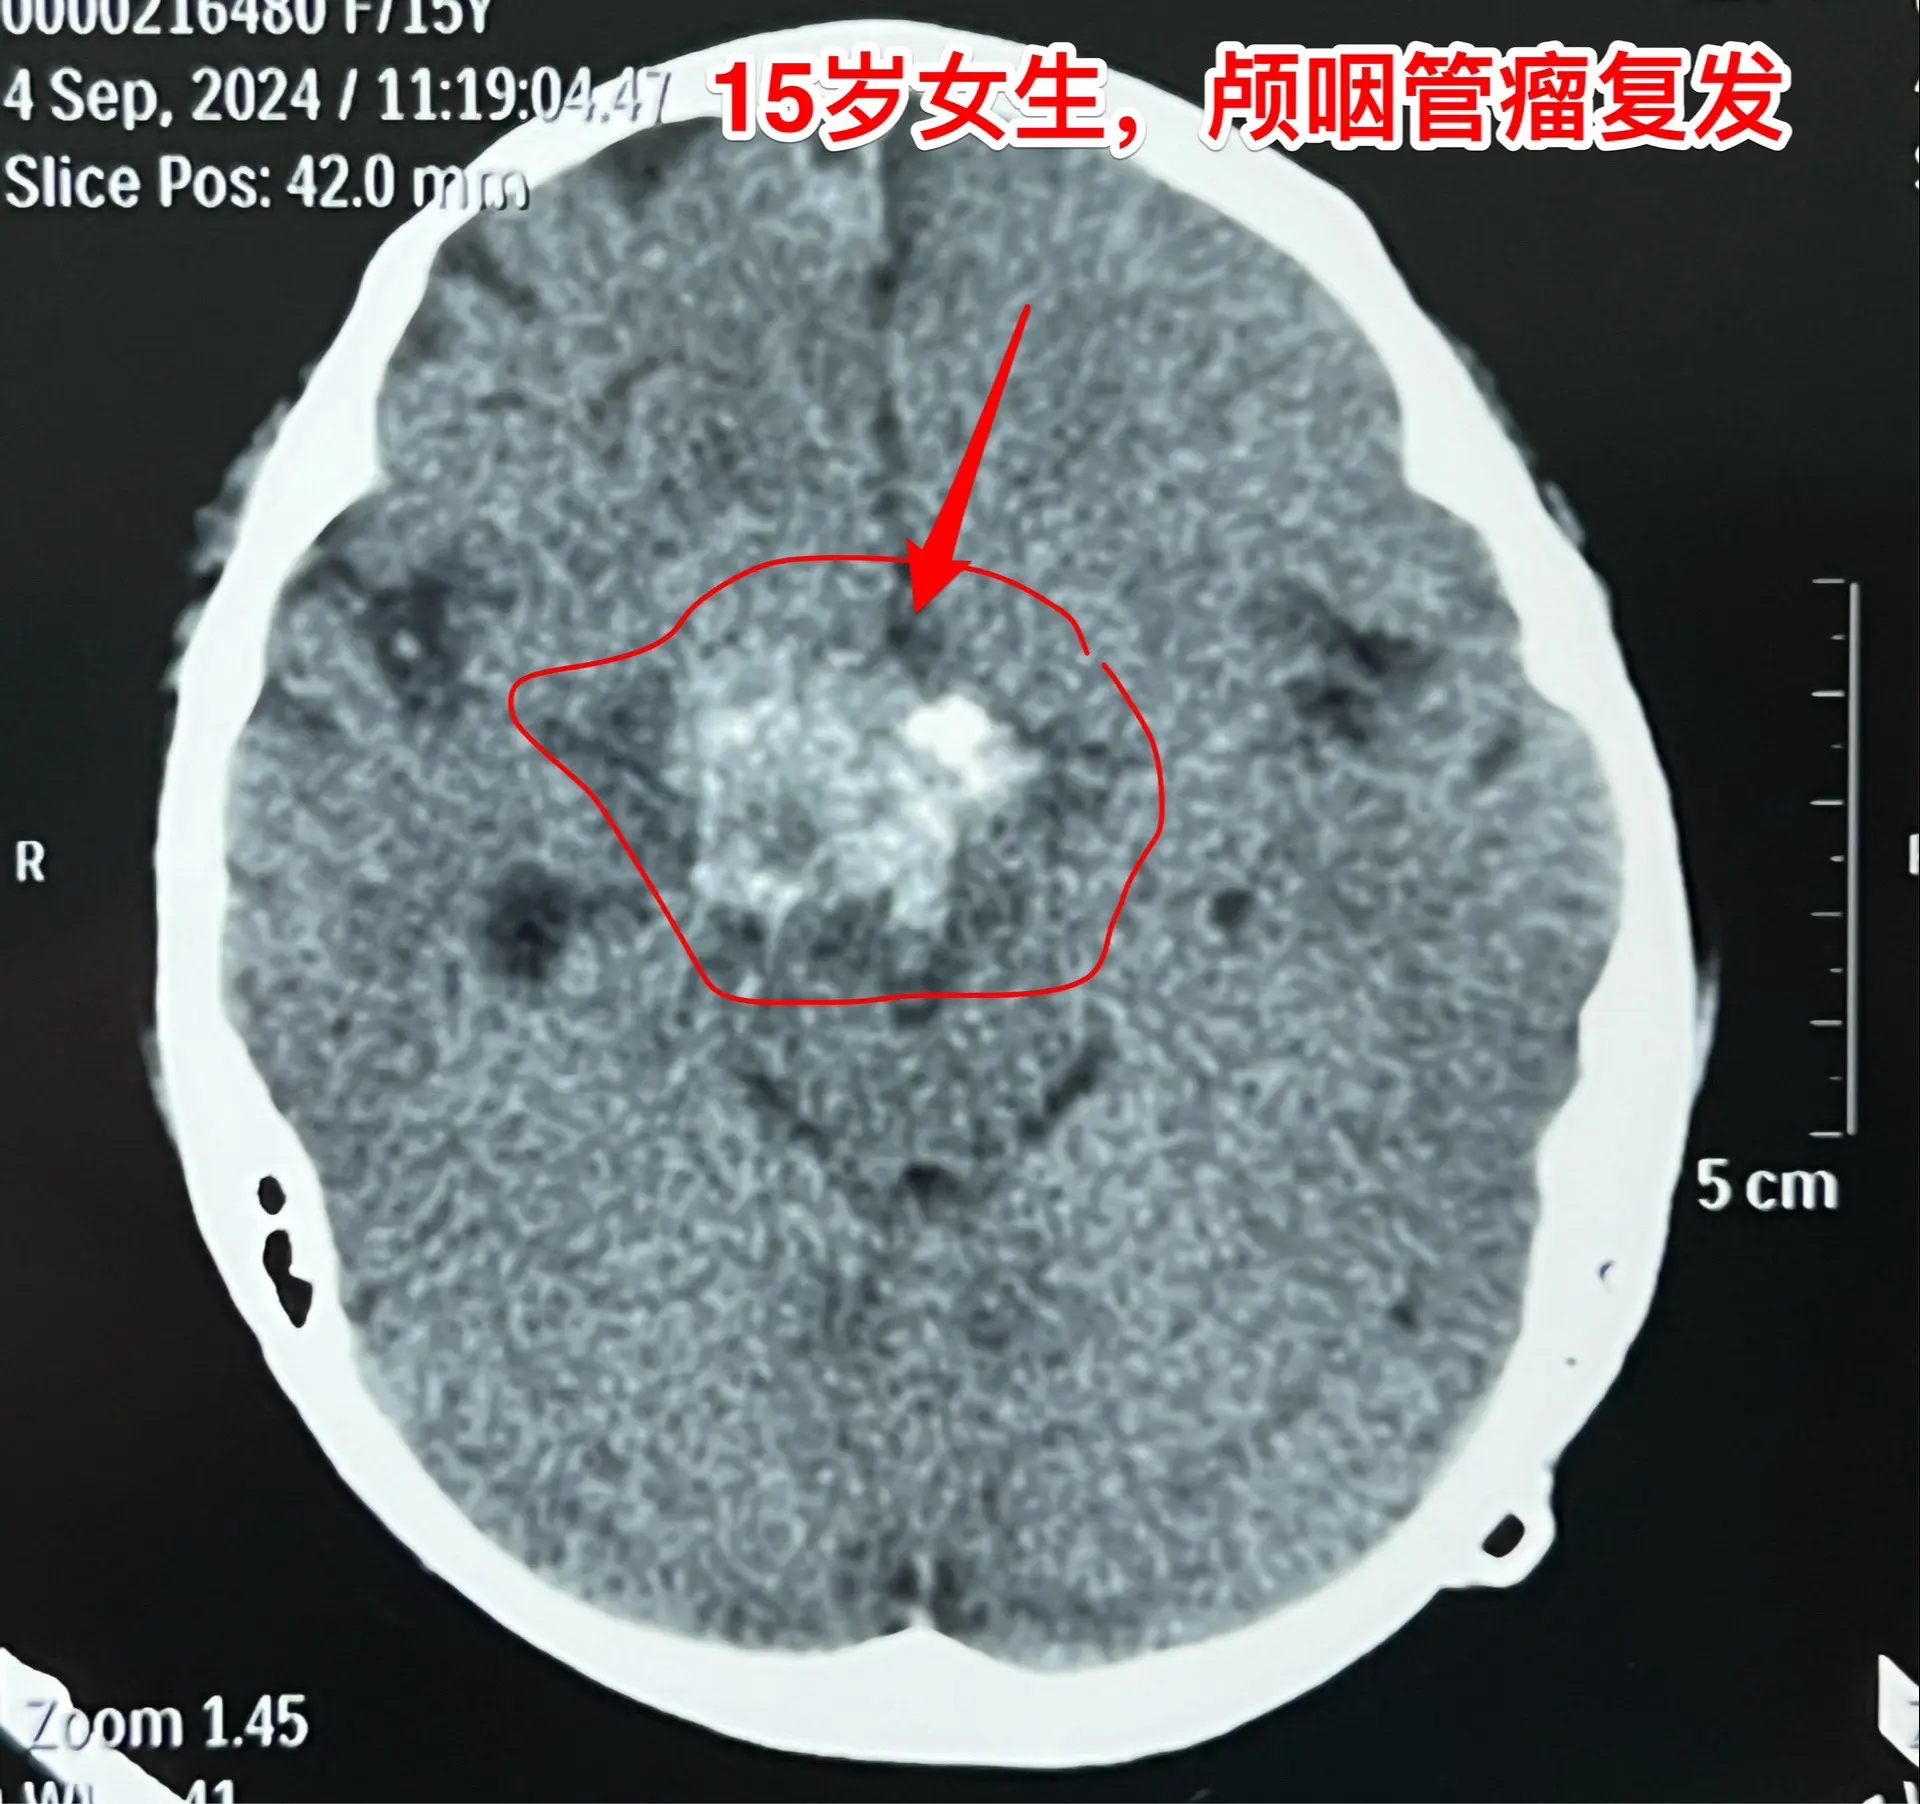

颅咽管瘤不是按匀速生长,进展很难预料。15岁的福建龙岩市女生,因颅咽管瘤之前在上海作过一次开颅手术,只有左眼有有效视力。两年前就发现肿瘤复发了,多次复查磁共振,显示肿瘤生长速度缓慢。2023.8复查磁共振见图,无明显症状,家长主张继续观察。今年八月患者出现症状,复查磁共振显示肿瘤体积显著增大,见图。所以说,颅咽管瘤的生长速度不是匀速的,医生也无法预测疾病的进展情况。

9月11日作了手术,经纵裂入路顺利切除肿瘤。经过仔细对比之前的磁共振,找到了复发肿瘤的起源点,才确定了这个手术入路。手术后患者语言、运动能力均好。发热持续时间比较长,经用抗菌药治疗后平稳了,十一前出院了。